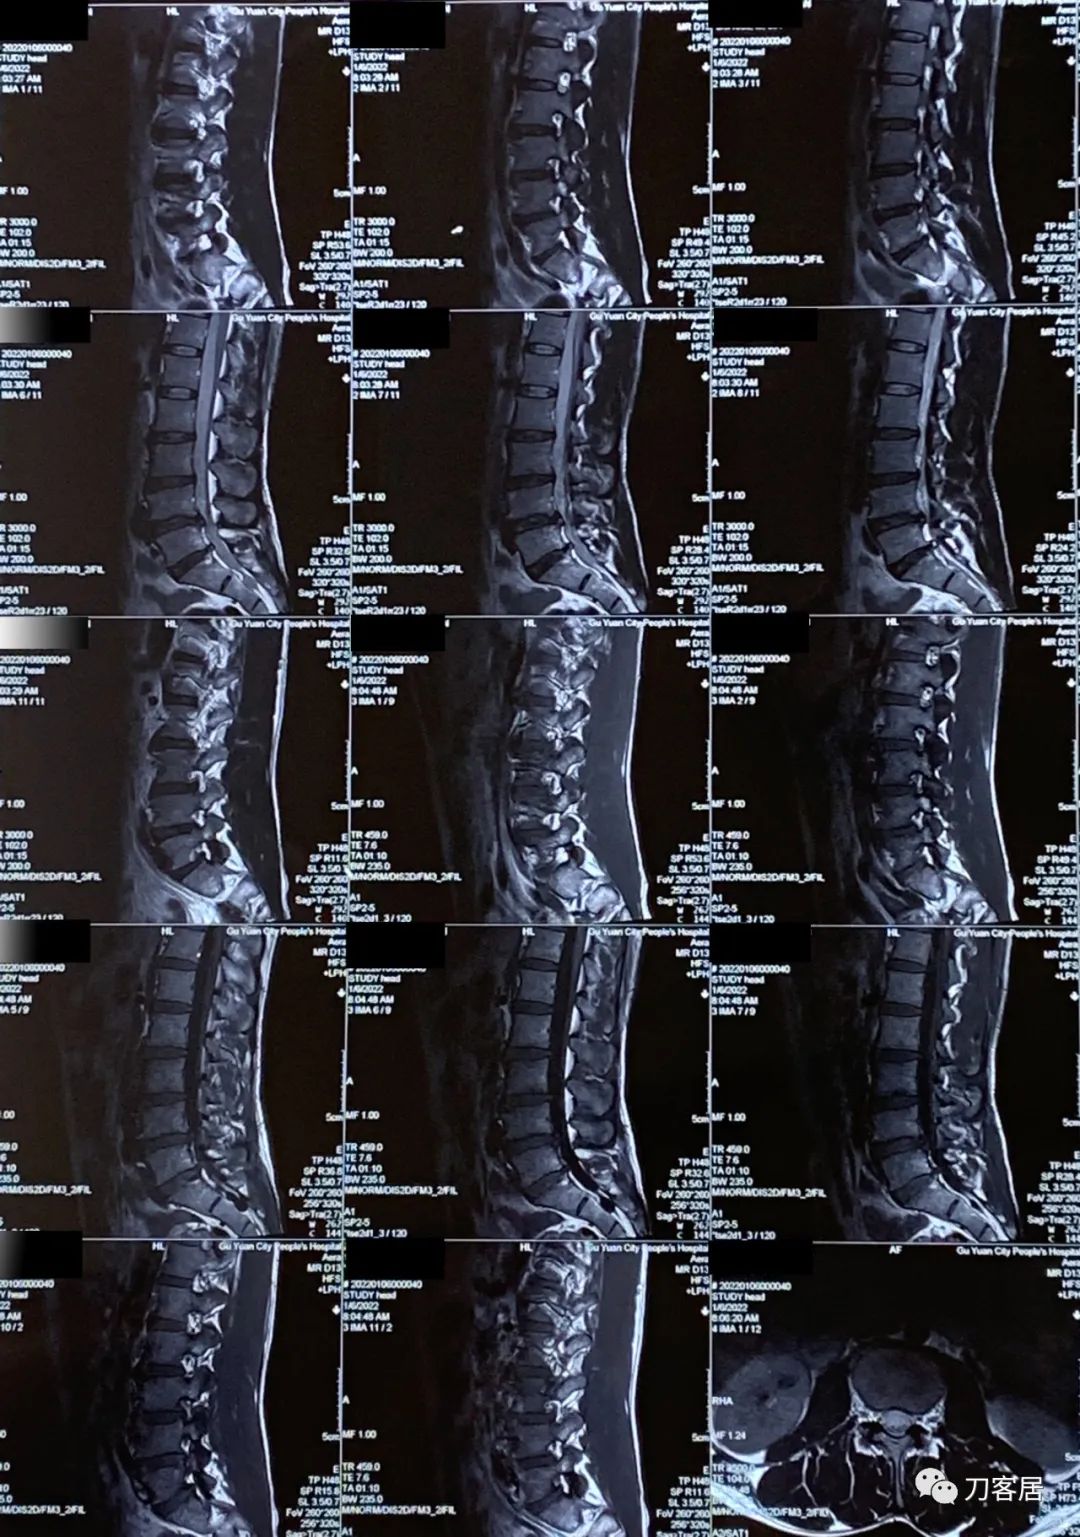

当地医院就诊时,考虑为腰椎间盘突出症,让患者做了腰椎MRI。患者来就诊时带着当地医院给做的腰椎MRI。在腰椎MRI上可见有腰4-5、腰5骶1椎间盘突出,但患者的临床表现有符合椎间盘突出之处,比如左臀部至足背抽痛,但行走不稳,容易摔跤,没法用腰椎间盘突出来解释,所以,就推荐患者到其他医院就诊。

图1. 20220106当地医院腰椎MRI01

图2. 20220106当地医院腰椎MRI02